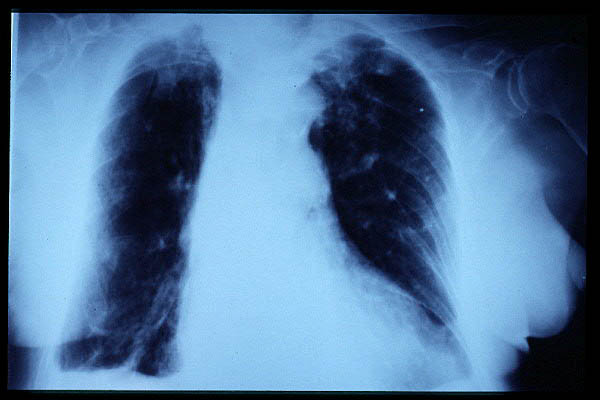

TBC pulmonar antigua